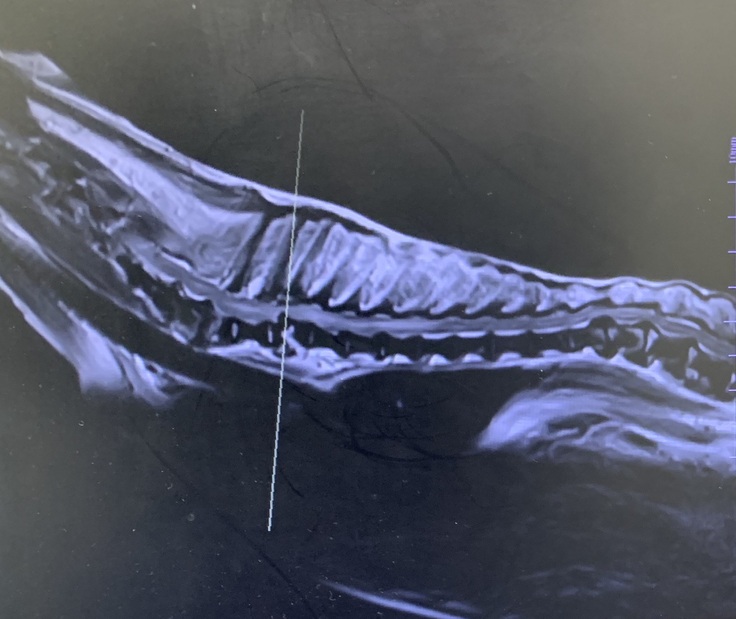

獣医師の先生から告げられたのは、胸椎の3番目の椎体が脱臼し脊髄を損傷したために脊髄障害を起こしているということ。そのため、様々な異常な行動を引き起こし、後ろ足が動かなくなってしまったというのです。

手術によって脱臼した椎体を元の位置にプレートで固定する方法があるのですが、モコの場合は脱臼した椎体が心臓や肺に近いため、手術によって心肺に障害を与えてしまうリスクがあるといいます。また、手術をしても脊髄障害を治すことは難しいそうです。さらに、14歳という高齢のため長時間の手術に耐えられない可能性もあるというのです。

MRI検査によるモコの胸部画像